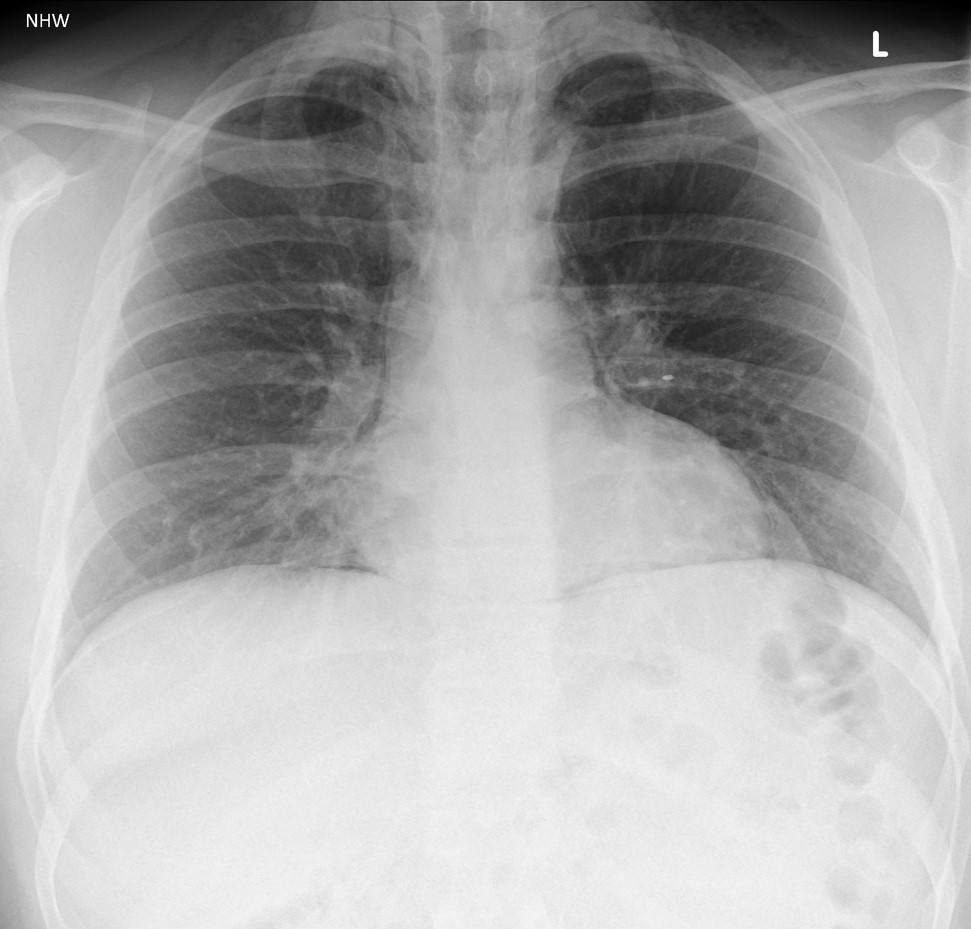

Tràn khí trung thất

Tràn khí trung thất - Ảnh 5

» Thông tin: Nam giới – 25 tuổi.

» Lâm sàng: Đau ngực.